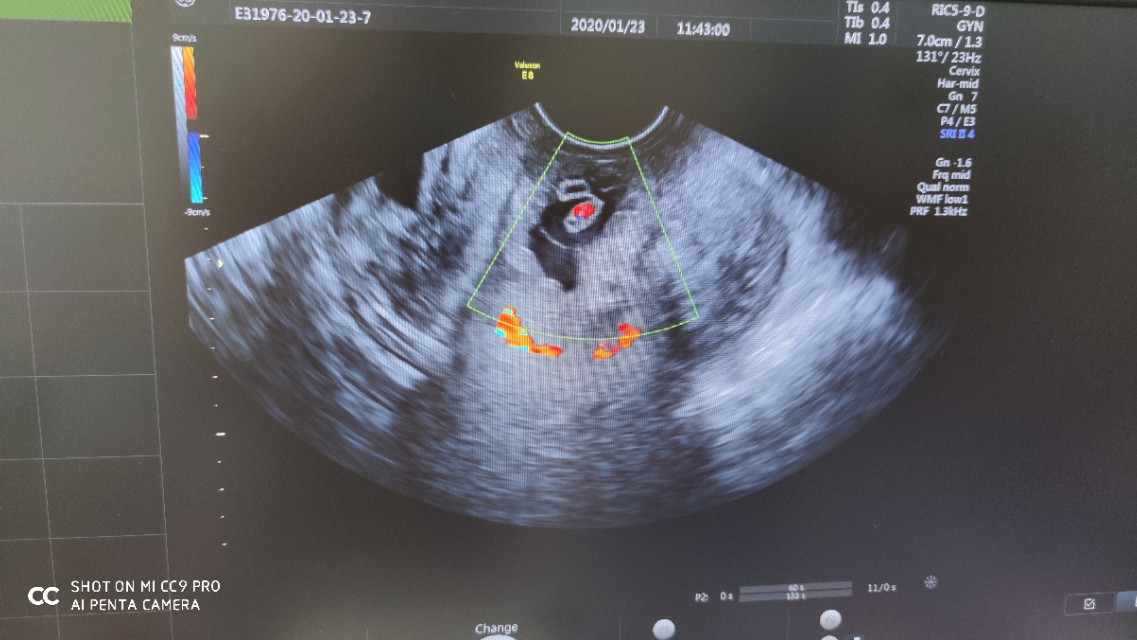

紧急将患者推往妇产科B超室,行阴式超声检查示:宫颈前唇膨大,内见孕囊,提示宫颈妊娠,见心管搏动。阴道内见大量凝血块,大量鲜血流出。

妇产科医生精确诊断为--异位妊娠:宫颈妊娠,失血性休克,立即启动应急预案,建立静脉通路、输血、实施阴式取胚术。